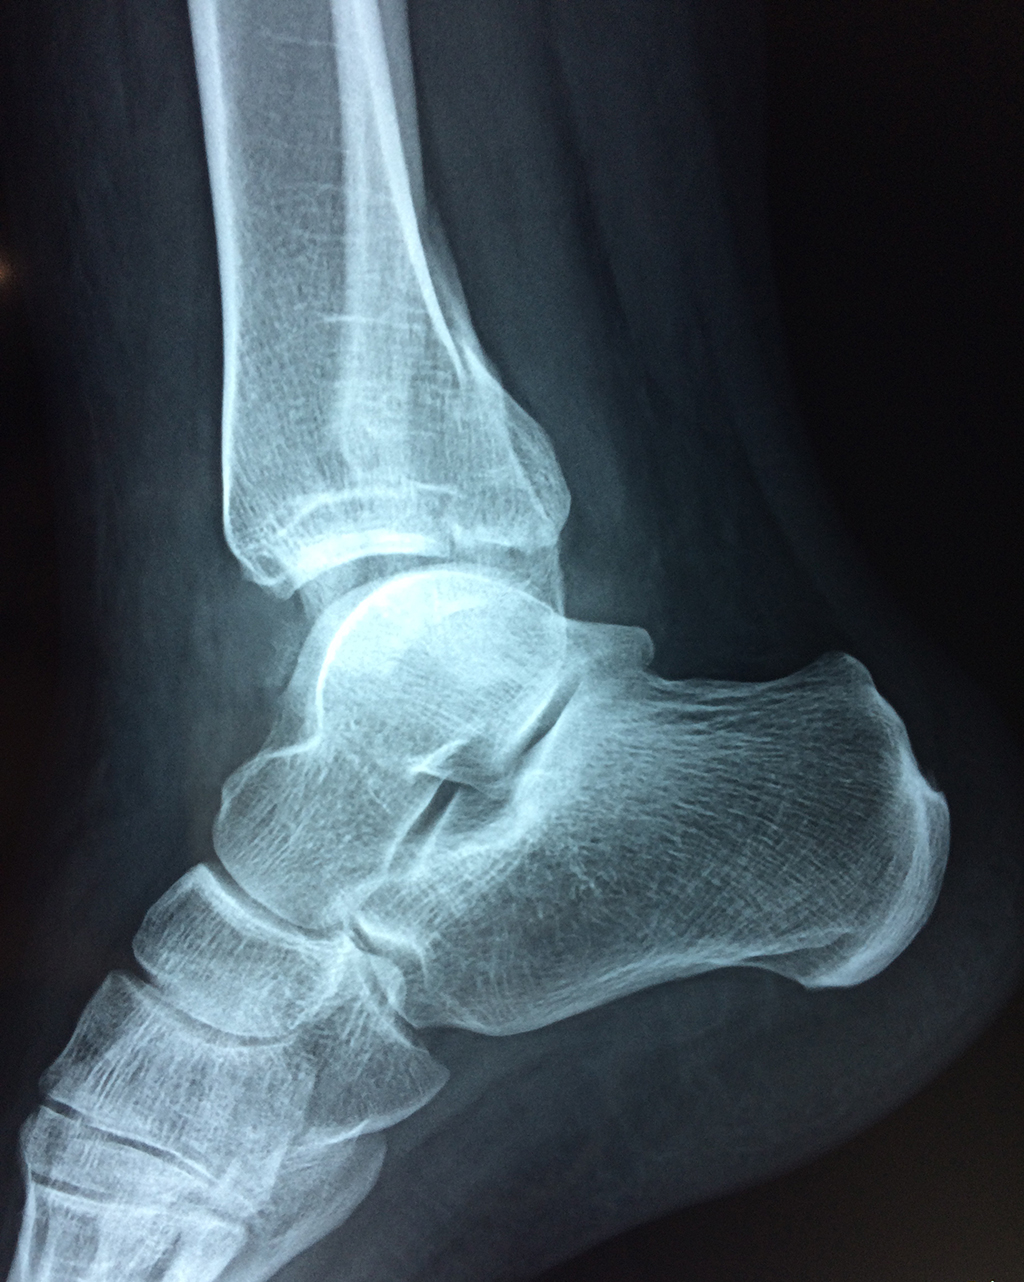

Una fractura de tobillo es la rotura de uno o más de los huesos del tobillo. Estas fracturas pueden ser:

- Parciales (el hueso está sólo parcialmente fisurado, no del todo).

- Completas (el hueso está perforado y está en 2 partes).

- Producirse en uno o ambos lados del tobillo.

Algunas fracturas de tobillo pueden requerir cirugía si:

- Los extremos de los huesos están desalineados entre sí (desplazados).

- La fractura se extiende hasta la articulación del tobillo (fractura intra-articular).

- Los tendones o ligamentos (tejidos que sujetan los músculos y los huesos entre sí) están rotos.